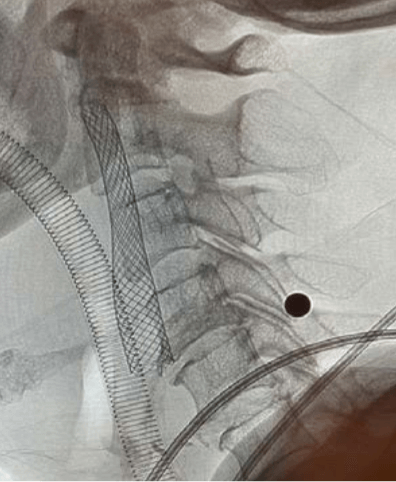

Mr. Lo’s being taken to a private hospital, an emergency MRI was done right away, which showed that the blood vessel in his right neck and brain was blocked by blood clots, ischemic edema in his right brain, which led to coma and weakness in his left hand and foot. Urgent Cerebrovascular surgery for the patient is needed, the doctor with a thin hair catheter through the patient’s right thigh groin to the main artery, catheter through the abdomen and chest cavity of the main artery all the way up, to the patient’s right neck and brain vessel, mechanical thrombosis absorption of internal vascular treatment was done. After an hour of vascular surgery, all blood clots were removed, blood vessels in the right neck and brain were successfully opened, and the symptoms of ischemic brain were immediately improved. After awake under general anaesthetic, Mr. Lo’s brain awareness and ability to move hands and feet slowly improved, and he was taken to another public hospital for further rehabilitation. For six years, Mr. Lo has been able to continue working and enjoy life with his family, except for a mild hand weakness. Mr Lo’s stroke treatment was six years ago, and in these years the emergency care for stroke in public hospitals has gradually improved to provide better services to patients.

The stent were inserted into the arteries to prevent future blockage